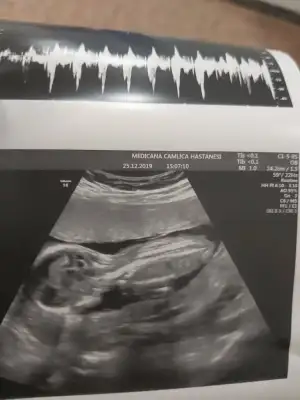

dr soylemeden siz gorun genital nub teorisi ( bebegin cinsiyeti)

Siz de yine bakarmısınız net söyledi kız diye herkes erkek demişti sizin gibi bende öyle diyordum ama ters köşe yaptı galiba bizimki çok hareketliydi 🤭🤣

• 20191225_151558.webp

20191225_151558.webp

20,2 KB · Görüntüleme: 46